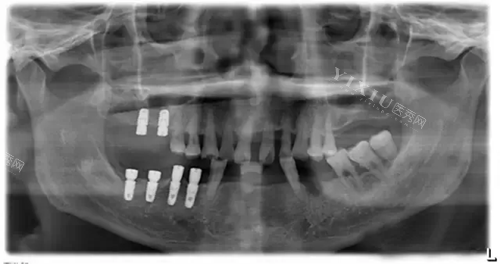

2009年,爷爷在平湖市某口腔医院种了奥齿泰种植牙。医生曾小林给他做了多样化检查:“您这牙槽骨条件不错,但缺牙时间太长,骨量有点萎缩,得选个骨结合能力强的种植体。”当时奥齿泰刚进入我国市场不久,但医生的话给了爷爷信心:“这牌子在韩国用了二十多年,表面有纳米涂层,能刺激骨头生长,适合您这种情况。”

“别看我这口牙现在风光,当年选型号时可没少纠结。”爷爷掏出手机,翻出当年医生给的方案表:“医生给我列了四个系列,US、TS、SS、MS,每个系列适应症都不一样。”

US系列:适合骨质好的后牙修复,价格3580元起步,爷爷的后磨牙就选的这款,“经济实惠,啃东西不心疼”。

TS系列:骨结合强化型,适合轻度骨量不足,价格4000元起步,爷爷的朋友老张头骨质差,种的就是这款,“愈合快,3个月就能正常吃饭”。

SS系列:生物活性型,钛锆合金材质,适合糖尿病或吸烟者,价格5500元起步,爷爷的邻居王奶奶有糖尿病,种的就是这款,“10年了,牙根从来没发过炎”。

MS系列:全口重建型,适合无牙颌,价格4500元起步,爷爷的老战友李爷爷全口缺牙,用了All-on-4技术,“半口6颗种植体,当天就能戴牙,现在吃嘛嘛香”。